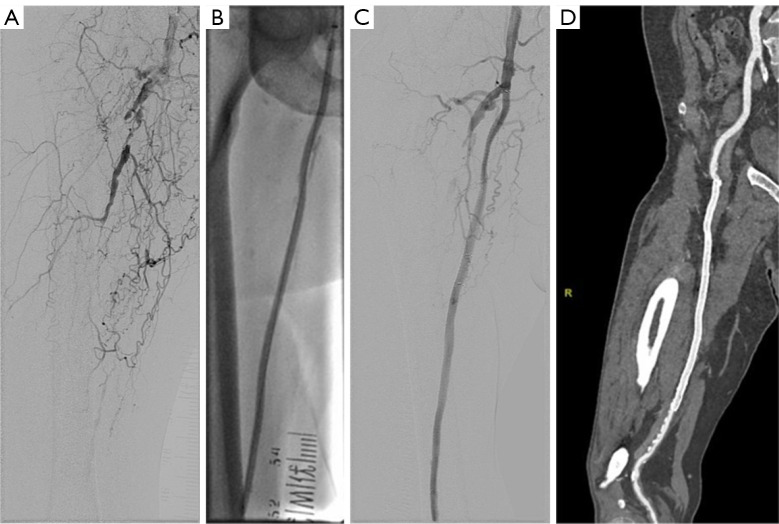

背景:药物传递装置已在临床试验中显示出疗效,并被广泛用于股腘动脉疾病。然而,对于复杂病变的最佳策略,如跨大西洋社会共识(TASC) C和D病变,在现实世界的实践中仍存在争议。本倾向评分匹配研究旨在比较双药策略[药物包被球囊(DCB)联合全身药物洗脱支架(DES)]和DCB救助策略(DCB +救助裸金属支架)对TASC和D股动脉病变患者的中期结果。方法:本研究为回顾性单中心研究,纳入2016年10月至2024年7月接受DCB治疗的TASC、C和D股腘静脉患者。倾向评分匹配(PSM)按1:3的比例进行,双药策略组1例患者对应DCB救助组3例患者。主要终点为24个月原发性通畅。次要终点包括无临床驱动的靶病变血运重建(CD-TLR)、死亡率、并发症、症状改善和再狭窄的危险因素。结果:经PSM后,对32对患者进行分析。基线特征平衡良好[标准化平均差(SMD)与DCB救助:64.5%对76.4%,P=0.76]。在24个月时,CD-TLR的自由度无显著差异(双药与DCB救助:95.8%对79.1%,P=0.20)。双药组卢瑟福分类改善显著(P=0.042)。两组间死亡率和并发症发生率相似。血脂异常被确定为原发性通畅丧失的独立预测因子[危险比(HR) =3.03, P=0.024]。结论:双药策略和DCB救助策略在TASC C和D病变中获得了24个月的通畅和无靶病变血运重建(TLR)。

Drug-coated balloon with bailout stenting versus drug-eluting stent plus drug-coated balloon in TransAtlantic Inter-Society Consensus C and D femoropopliteal lesions: a propensity score-matched analysis.